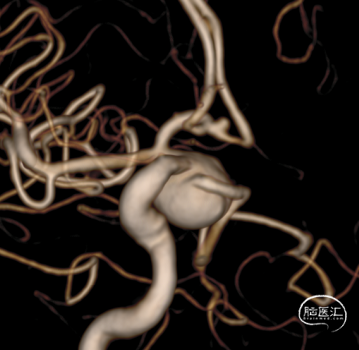

三维重建:后交通动脉起始部大动脉瘤,后交通动脉发自瘤体肩部。

三维重建:三维测量示动脉瘤大小约15.2mm*11.5mm,颈宽约8.2mm。

支架释放后三维旋转DSA:瘤腔内造影剂滞留,载瘤动脉通畅,各分支血管血运通畅。

支架释放完成后三维重建:载瘤动脉通畅,右侧后交通动脉和脉络膜前动脉保留完整。